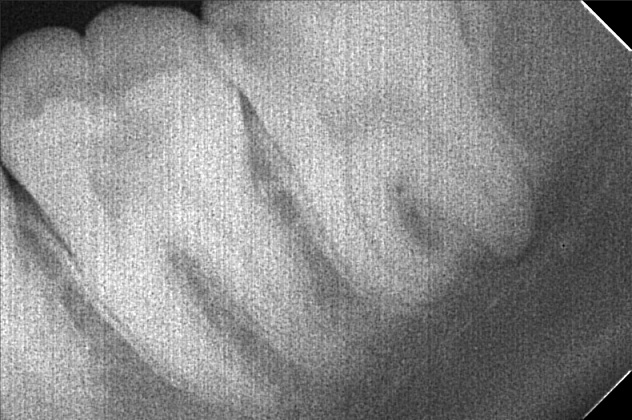

- ma-_zorina_cabas_02.jpg